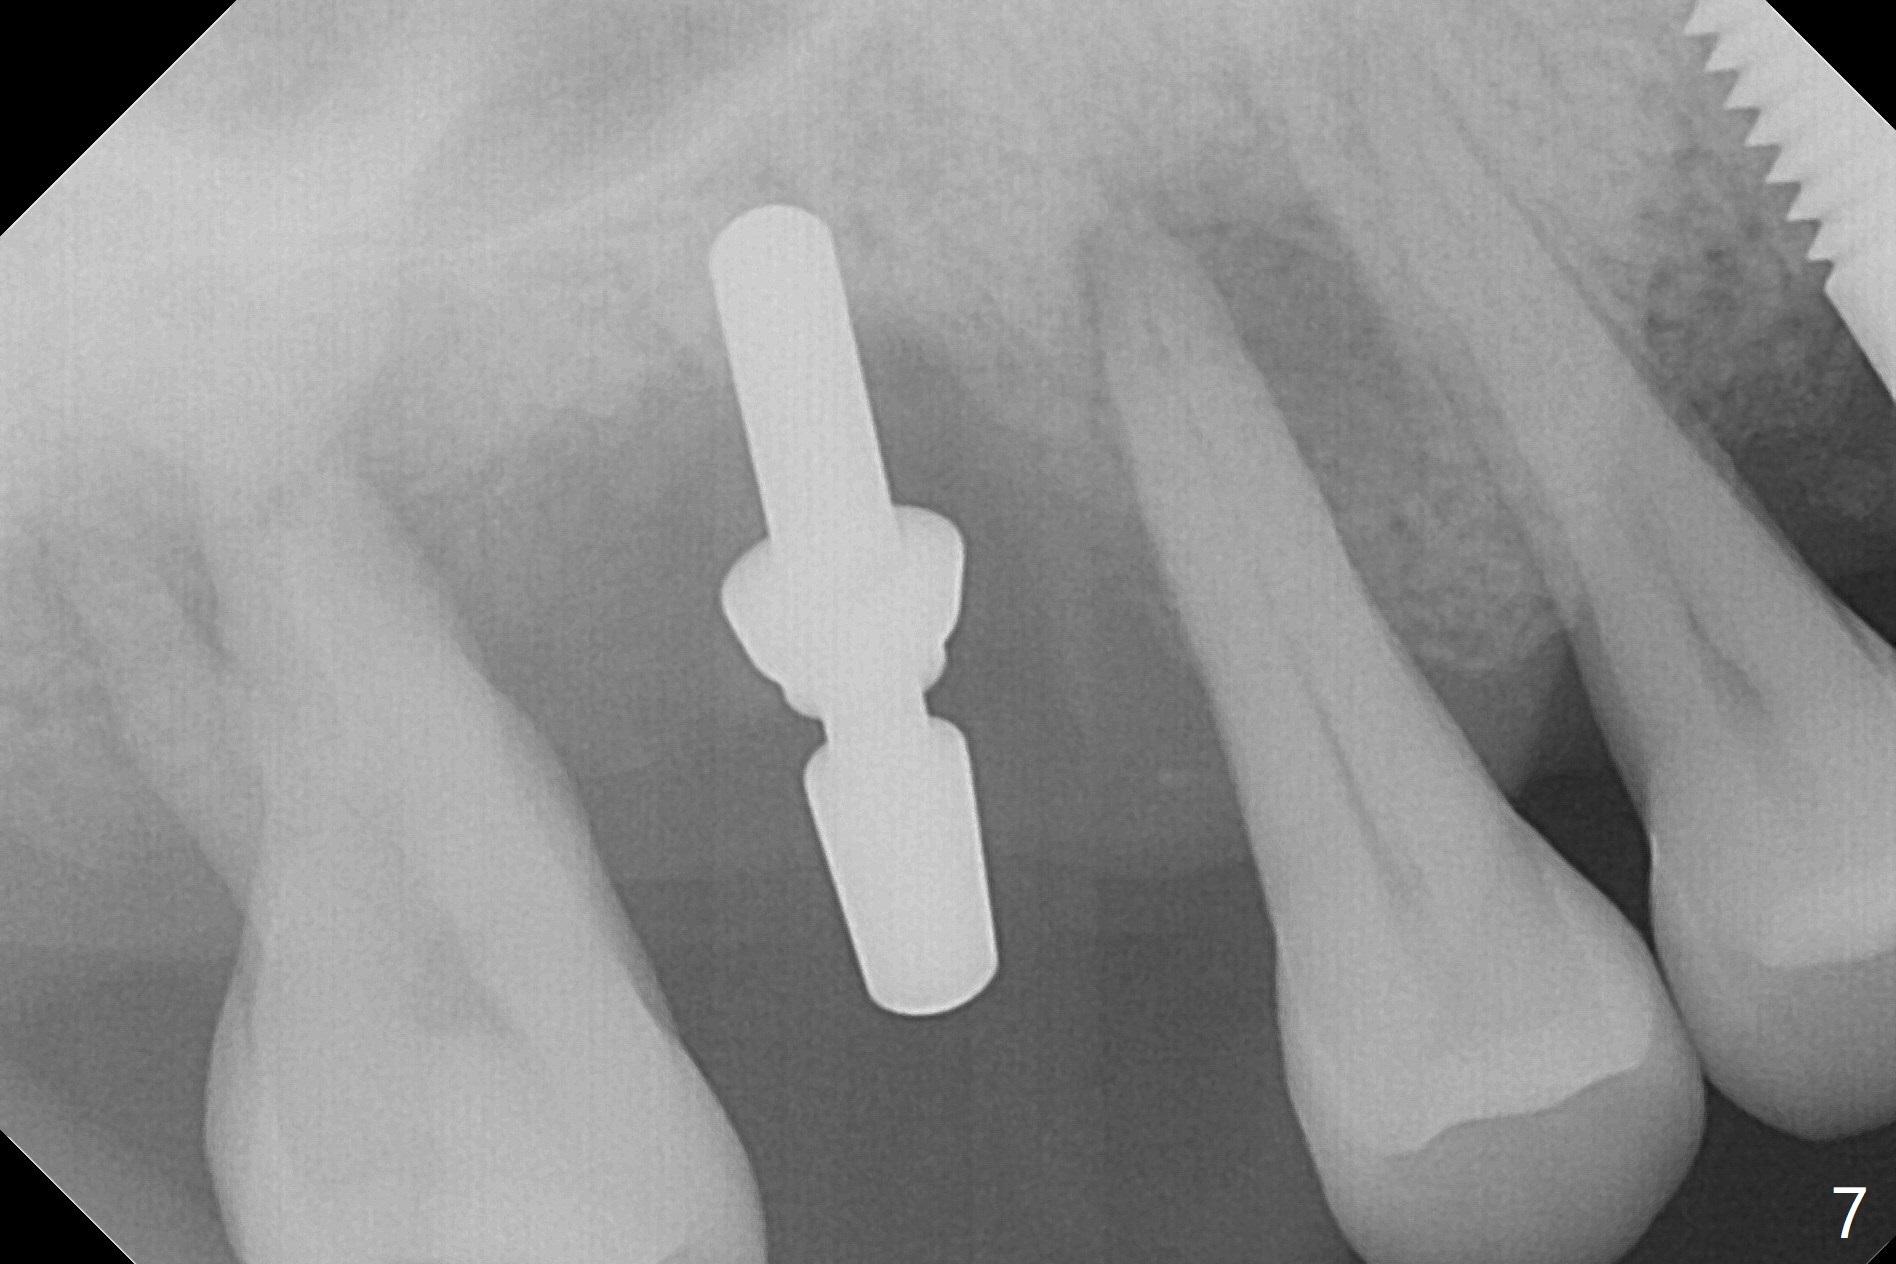

Initial osteotomy depth is 4 mm (Fig.7). The sinus membrane is found to be perforated when the depth increases to 8 mm. The latter could be prevented by taking CT and/or using osteotome. The subsequent osteotomy depth is 5 mm until 4.0 mm in diameter. When the 4.5 mm tap is inserted with initial stability, the shortest implant (8.5 mm, Fig.8 green) will be partially protruded into the sinus and partially exposed in the socket and the cuff of the abutment is expected to be around 6 mm (pink). Since the 5 mm tap achieves primary stability, a 5x8.5 mm implant (following placement of Osteogen plug to repair the perforated sinus membrane) is placed at the level just mentioned (Fig.9). Vanilla Graft mixed with minimal autogenous bone is packed (Fig.10.11 *) before and after insertion of a 6.5x5(4) mm abutment. An immediate provisional as well as a piece of Osteogen plug is fabricated to close the socket gap. The provisional and the abutment are dislodged 1 month postop (Fig.12). The wound has healed. The abutment is reloaded without the provisional. The implant appears to osteointegrate 4.5 months postop (Fig.13); in addition the bone graft seems to have migrated toward the roots of the neighboring teeth (arrows).